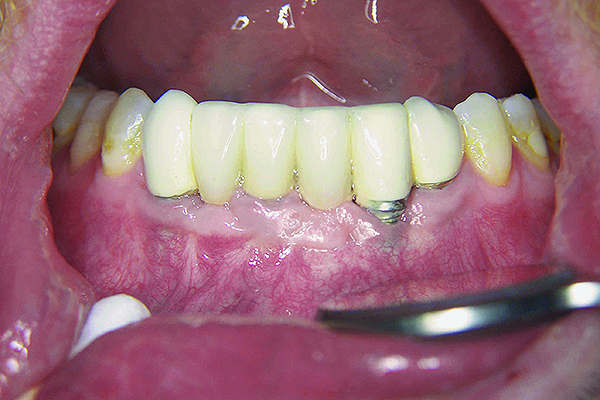

Fig 3. Bleeding on probing and increasing pocket depths around implant sites indicates a need for treatment.

Figure 3

Fig 7. Close-up view of the No. 23 implant-supported restoration showing inflammation surrounding the site (this area had not been grafted).

Figure 7